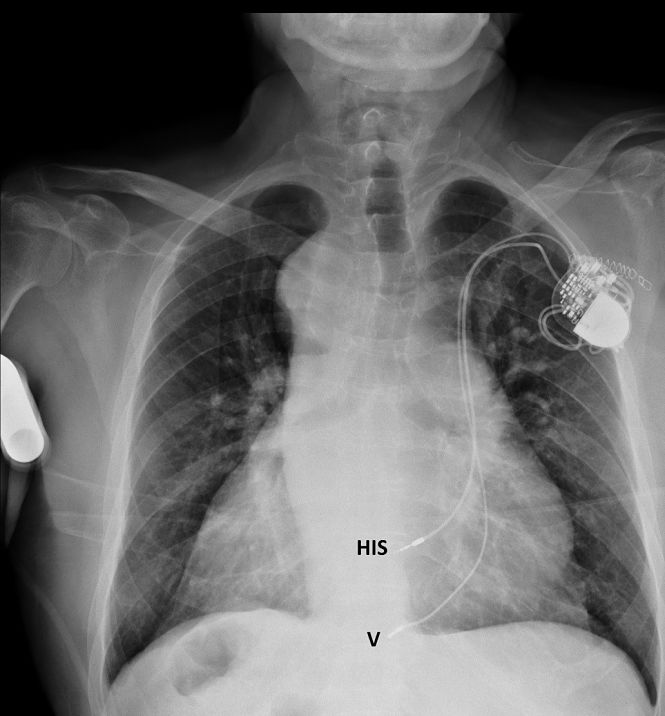

El Hospital Universitario Virgen de las Nieves de Granada ha realizado cerca de cien intervenciones para implantar un dispositivo con estimulación fisiológica que activa los ventrículos del corazón por su vía natural y de esta forma mantienen la fuerza de contracción del mismo y previenen el desarrollo de insuficiencia cardiaca.

Esta técnica conocida como la estimulación hisiana ha emergido en los últimos años y se caracteriza por usar las vías eléctricas presentes en el corazón que permiten una contracción del corazón natural y similar a la de cualquier persona sana.

El tratamiento habitual para esta bradicardia es la implantación de un marcapasos para llevar electricidad al corazón y poder estimularlo a una frecuencia cardiaca adecuada con lo que inmediatamente se resuelve el problema y las molestias que esta produce.

Sin embargo, en los meses y años siguientes el problema de los marcapasos convencionales es que la activación eléctrica de los ventrículos la hace de una forma anómala, distinta a la fisiológica, puesto que el cable del marcapasos se posiciona en el sitio donde llega más fácilmente que es el llamado ápex del ventrículo derecho.